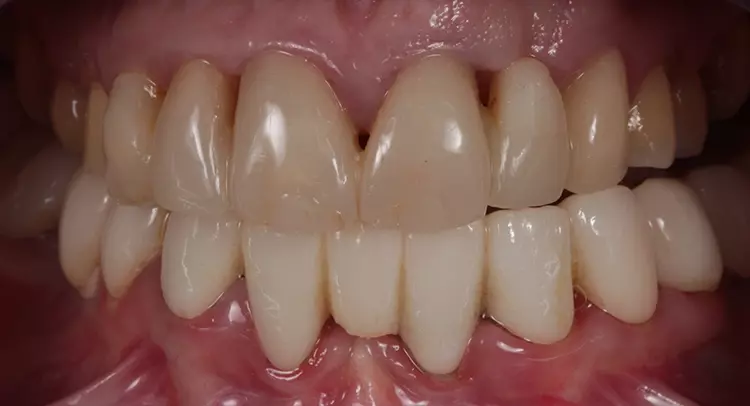

Eine 35-jährige Patientin stellte sich auf Empfehlung eines Kollegen mit einem sanierungsbedürftigen, parodontal (Parodontitis apicalis) geschädigten Gebiss vor. Zudem zeigten sich Verspannungen im Schulter- und Nackenbereich. Sie wies darauf hin, dass sich aufgrund einer angefangenen prothetischen Sanieriung in der jüngsten Vergangenheit das Kauvermögen deutlich reduziert hat und die Gebisssituation besonders in der oberen Front sich immer weiter verschlechtert hat. Laut eigener Aussage „würden die Zähne nicht mehr richtig aufeinanderpassen“ und seit der angefangenen Sanierung im UK „wäre das Kauen nur noch eingeschränkt möglich“ (Abb. 1 und 2).

Sie litt zudem an überempfindlichen Zahnhälsen im Bereich der Prämolaren und Molaren beidseits. Vor ungefähr 15 Jahren wurde laut Patientin die erste „Full-Mouth-Rekonstruktion“ in Mazedonien durchgeführt. Die klinische Funktionsanalyse zeigte positive parafunktionelle Befunde (okklusaler Index 1,4 „kompensiert +“), die bei der Patientin regelmäßig zu Kopfschmerzen sowie starken Beschwerden beim Kauen und Schlucken führten.